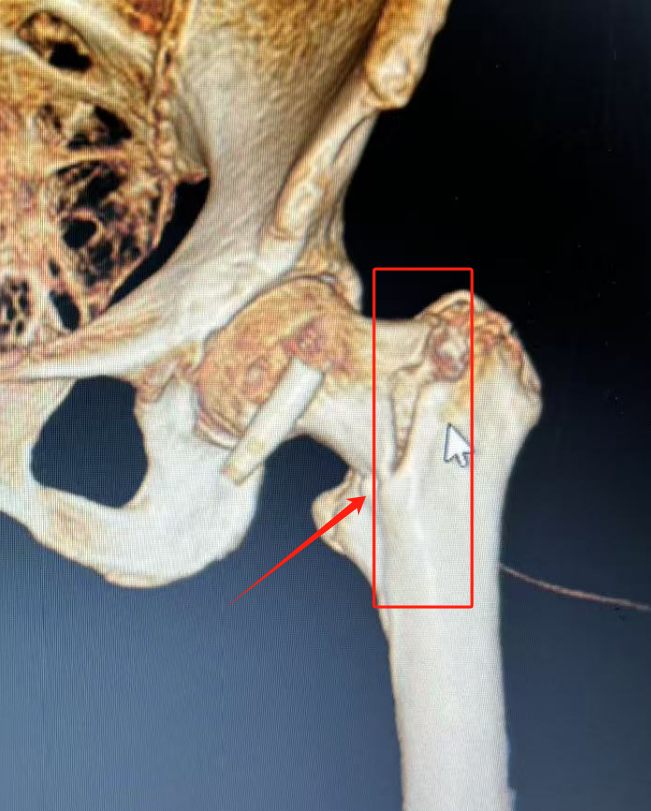

近日,百岁高龄的王奶奶在家中行走时摔倒致左髋部受伤,因“左侧股骨转子间骨折”收入骨科(创伤中心)住院治疗。股骨转子间骨折的患者需要手术治疗才能重新站立和行走,若不手术,患者只能长期卧床,“褥疮”、“下肢静脉血栓”等各种并发症将接踵而至,毫无生活质量可言,死亡率高。

骨科(创伤中心)负责人韩雪峰团队针对王奶奶年事已高,基础性疾病多,心脑肺储备功能差等病情,进行充分的术前评估,制定周密手术方案,在椎管内麻醉下行股骨转子间骨折闭合复位髓腔钉内固定术,手术非常成功。